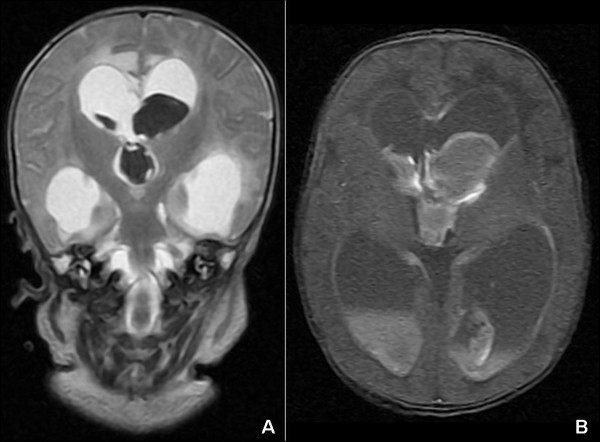

2. Hidrosefalus

Menurut National Institute of Neurological Disorders and Stroke (NINDS), hidrosefalus adalah penumpukan cairan yang tidak normal di ventrikel otak. Akibatnya, ventrikel melebar dan memberi tekanan pada jaringan otak.

Walau penyebab hidrosefalus belum diketahui secara pasti, gejalanya mudah dikenali, seperti ukuran kepala yang lebih besar daripada ukuran normal, mata melihat ke bawah, pembesaran kepala yang cepat, muntah, kejang, kesulitan mengisap atau menyusu, dan kantuk berlebih.

Salah satu cara untuk menangani hidrosefalus adalah dengan ventriculoperitoneal shunts untuk mengalirkan cairan ekstra keluar dan mencegah tekanan pada otak agar tidak terlalu tinggi, mengutip Kids Health. Opsi lain adalah dengan ventrikulostomi, salah satu prosedur pembedahan yang bersifat invasif.